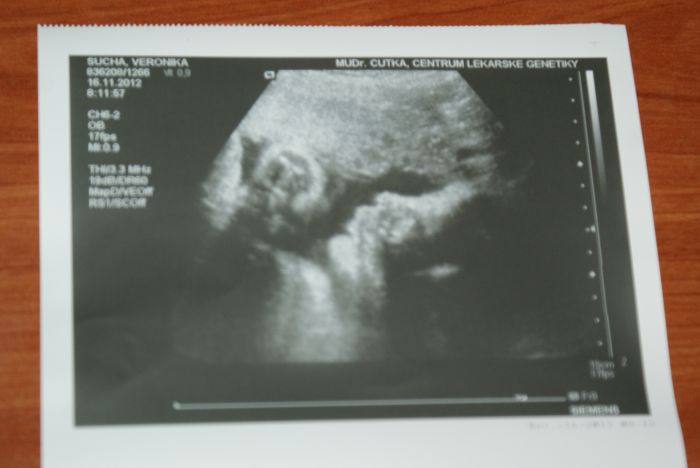

A fotečka mimíse

Tak to je skvělí Janči, že vás vzali. Já chodím jen na genetiku, protože moje Mudr. nemá UZ, tak tam chodím od začátku...tentokrát jsme měli štěstí na mladého Čutku, jak říkám hlavně ne starýho

No já jsem zvědavá komu bude podobnej, ale podle UZ fotky, která je úplně jiná než když jsem čekala fotku, ta je celá táta, asi to vypadá, že bude po mě

Uvidíme až se narodí. Taky byl vklidu občas mírně kopnul jak ho tam pořád otravoval tím UZ, ale naštěstí nic šíleného